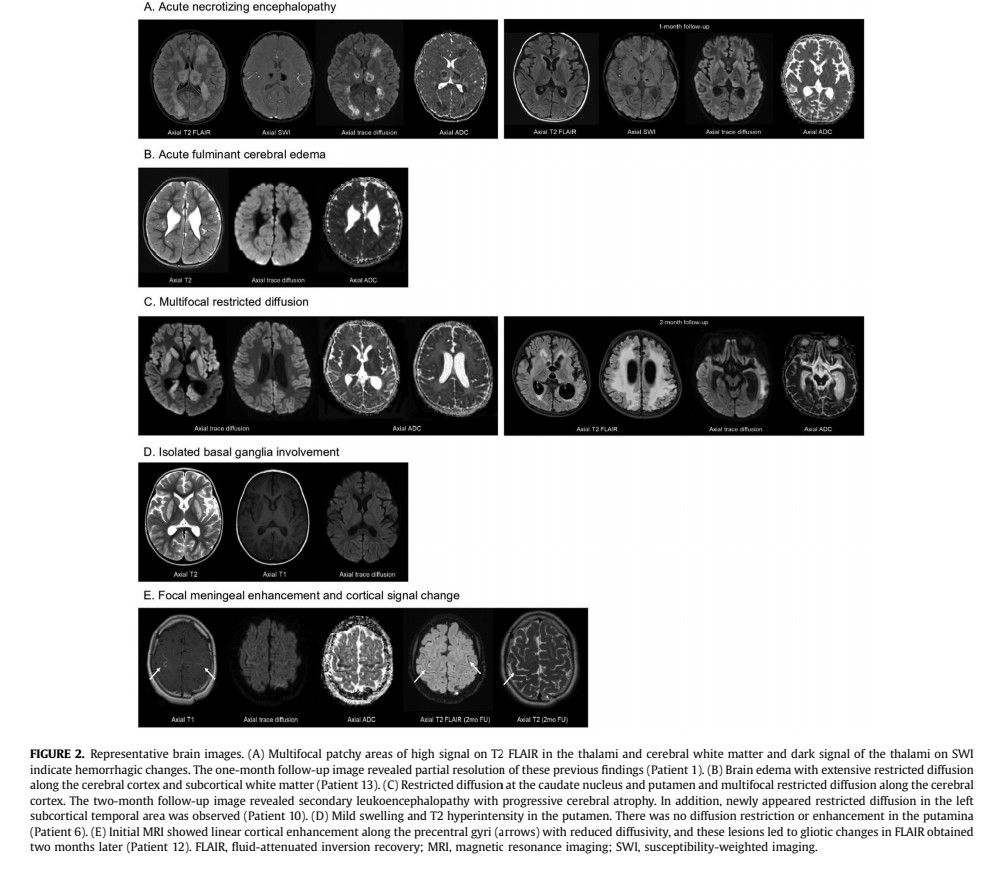

Severe neurological manifestations included acute necrotiwezing encephalopathy ... Image

4) ...acute fulminant cerebral edema, acute disseminated encephalomyelitis, basal ganglia encephalitis, severe encephalopathy/encephalitis, and refractory status dystonicus.

MRI findings showed various patterns of abnormalities including lesions with restricted diffusion ... Image

5) ...in the cortex, subcortical white matter, basal ganglia, and thalamus.